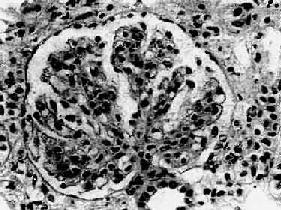

图12-13 膜性增生性肾小球肾炎

肾小球系膜细胞增多,增生的系膜组织侵犯毛细血管,毛细血管壁增厚,腔狭小,肾小球丛呈分叶状

肾小球系膜细胞和基质增生。系膜区增宽,其间常有数量不等的中性粒细胞浸润。增生的系膜组织逐渐向周围毛细血管伸展,侵入毛细血管基底膜与内皮细胞之间,使毛细血管壁增厚,管腔狭窄(图12-13)。应用银染法可见增厚的毛细血管壁呈车轨状或分层状。由于系膜增生,系膜区增宽,使毛细血管丛呈分叶状。严重时可使轴心处呈结节状。病变继续发展,增生的系膜组织可环绕全部毛细血管壁,使管壁显著增厚,管腔狭小甚至阻塞。有时部分肾小球内可有新月体形成。晚期,系膜及肾小球纤维化、硬化,整个肾小球形成无结构的玻璃样小团。相应的肾小管萎缩,间质纤维组织增生,有多数淋巴细胞及单核细胞浸润。